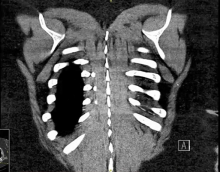

The patient was a 31-year-old woman with prior episodes of asthma exacerbation who was diagnosed incidentally with an intralobar pulmonary sequestration of the posterior basal left lower lobe. CT scan demonstrated an arterial feeding vessel to the sequestration originating from the celiac artery of the abdominal aorta. Surgical resection was recommended. Given the size, origin, and location of the feeding vessel to the sequestration, the authors elected to coil embolize the feeding artery prior to surgery to facilitate a safe thoracoscopic approach. The patient underwent thoracoscopic left lung basilar segmentectomy the next day. The large aberrant vessel was identified, dissected, and divided using a tan stapler at the level of the first bifurcation. The basilar arteries were subsequently divided with an endoscopic stapler, and the superior segmental artery was spared. The basilar segmental bronchus and inferior pulmonary vein distally to the branch feeding the superior segmental vein were isolated and divided, individually. The basilar segment was then separated with parenchymal stapling. The specimen was placed in a lobectomy bag and extracted through the wound. Intercostal nerve blocks were provided with liposomal bupivacaine. The patient tolerated the procedure well. The patient was discharged on postoperative day two and seen for follow-up at four weeks with no complications.